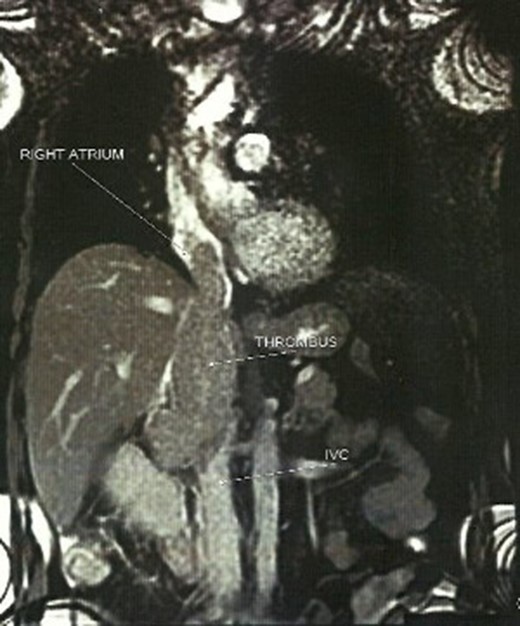

A 66-year-old male, former smoker with a history of hypertension, chronic obstructive pulmonary disease and glaucoma was delivered to the emergency department after a presyncope episode. The patient mentioned episodes of diarrheic melaenas over the last 2 weeks, a progressively worsening dysthymia over the last 2 months and a constant pain of the right lower lumbar region of more than five months that was diagnosed as a hernia. ECG showed sinus rhythm with frequent atrial ectopics. The clinical examination was without special findings and malaena was not clinically confirmed. Vital signs were measured within normal limits. Laboratories revealed anemia (Hct 30.4%, Hb 9.8%), mild elevation of liver enzymes (gGT 197, ALP 186) and CRP (14.1 mg%). Cardiac markers and fecal occult blood test were negative. An abdominal ultrasound revealed a heterogenous mass (6.8 × 6.7 cm2) on the upper pole of the right kidney and a tumor thrombus extending to the IVC. The CT scan of the abdomen and the thorax confirmed the diagnosis of renal mass with cavoatrial tumor thrombus. Pre-surgical staging with MRI and angiography revealed no other sites of pathology or metastasis (Fig. 1).

The patient underwent a radical en bloc nephrectomy and thrombectomy under extracorporeal circulation in normothermia and beating heart. The patient remained on ICU for 7 days and on the fourth day, following oedema of the right lower leg, a femoral and iliac vein thrombus was discovered. This was corrected surgically and no other complications were incurred. He was discharged on Day 19. Two years postsurgery a possible retroperitoneal tumor was detected and removed by a median laparotomy. Histology did not reveal any features of malignancy. The patient, 4 years after initial surgery, is under oncological follow-up, receives targeted therapy and no other sites of metastasis have been found yet.